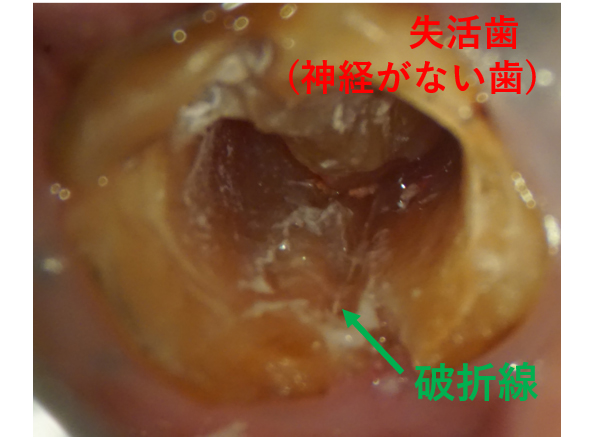

歯根破折が起こりやすくなる(歯が脆くなり、割れやすくなる)

歯根破折とは、歯の根が折れたり割れたりすることを言い、歯根破折が起こってしまうと、ほとんどのケースで抜歯をせざるを得なくなってしまうため、なるべく避けたい怖い症状のうちの一つです。

歯根破折の原因はさまざまですが、噛む力が強すぎたり、食いしばりや歯ぎしりの癖などにより引き起こされることも多く、近年、徐々に増加傾向にあります。

歯根破折は、年齢にもよりますが、神経のある歯の場合はに起こることがなく少なく、ほとんどが神経の無い抜髄済みの歯に起こります。

神経の無い歯は水分や栄養分を失っているため、枯れ木のように「しなり」を失い、割れやすく、折れやすくなっているためです。

※神経のある歯でも、負担が蓄積された中高年層の場合は、破折が起こる時もあります。